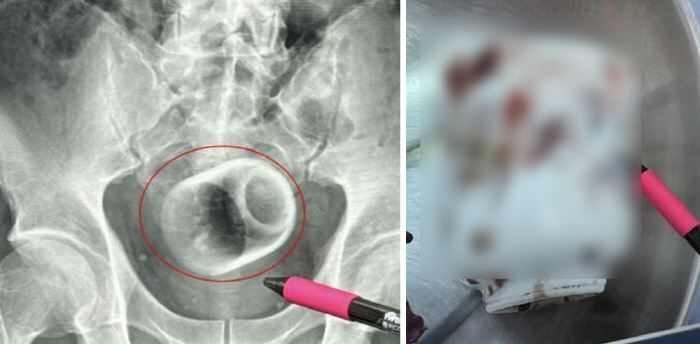

On X-ray examination, the medical team found that a ceramic cup measuring 6cm in diameter and 8cm in height was located inside the man's anus. Initially, the removal was attempted using a medical device, but the surface was smooth and failed. Eventually, it was safely taken out through an abdominal incision.